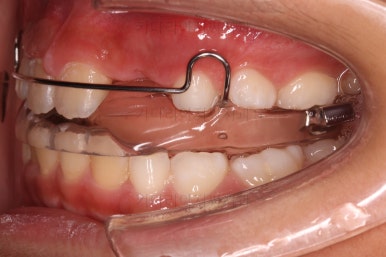

문제가 되었던 치아를 제위치 시켜준 뒤에 본격적인 성장교정을 시작했어요.

입안에 착용한 장치는 식사시간 제외 20시간 이상 사용이 추천되는 액티베이터라는 장치입니다.

이 장치는 성장이 부족한 아래턱을 앞으로 내밀어주게 되는 장치입니다.

또 다른 장치를 함께 사용해 주었는데요.

머리에 착용하는 헤드기어라는 장치입니다. 이 장치는 잘 때 위주로 해서 12시간 가량을 사용하게 됩니다.

이 환자분은 위턱이 크고 + 아래턱이 작은 즉, 위턱과 아래턱의 복합ㅈ거인 문제가 있었던 케이스였어서 각각에 대한 치료를 동시에 진행한거죠.

헤드기어는 과잉성장이 있는 위턱의 성장을 억제하고 가능한 범위에서 약간 뒤로 당겨주는 장치입니다.

점점 아랫니-윗니가 가까워지고 있어요.

특히 아래턱이 작을 경우 거의 필연적으로 생기는 과개교합(아래 앞니가 윗니에 매우 많이 가려져 있는 증상)도 상당히 많이 개선이 됩니다.